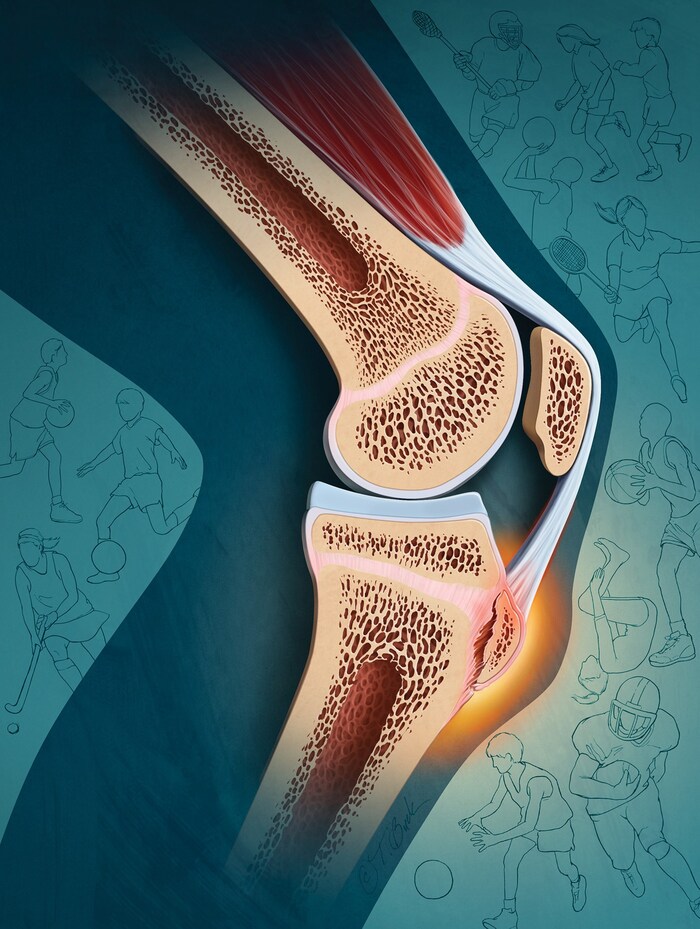

К бугристости большеберцовой кости (под коленом) крепится связка надколенника. Данная связка - сухожилие прямой мышцы бедра (часть четырехглавой мышцы). Пи частом сгибании коленного сустава, мышца напрягается. Она укорачивается. Начинает тянуть за собой точку прикрепление с надкостницей. Возникает отек и болезненность.

Частая причина обращения подростка- спортсмена к ортопеду - боль под коленом в области бугристости. В большинстве случаев - Болезнь Шляттера (изменения в бугристости большеберцовой кости)

Болит под коленкой